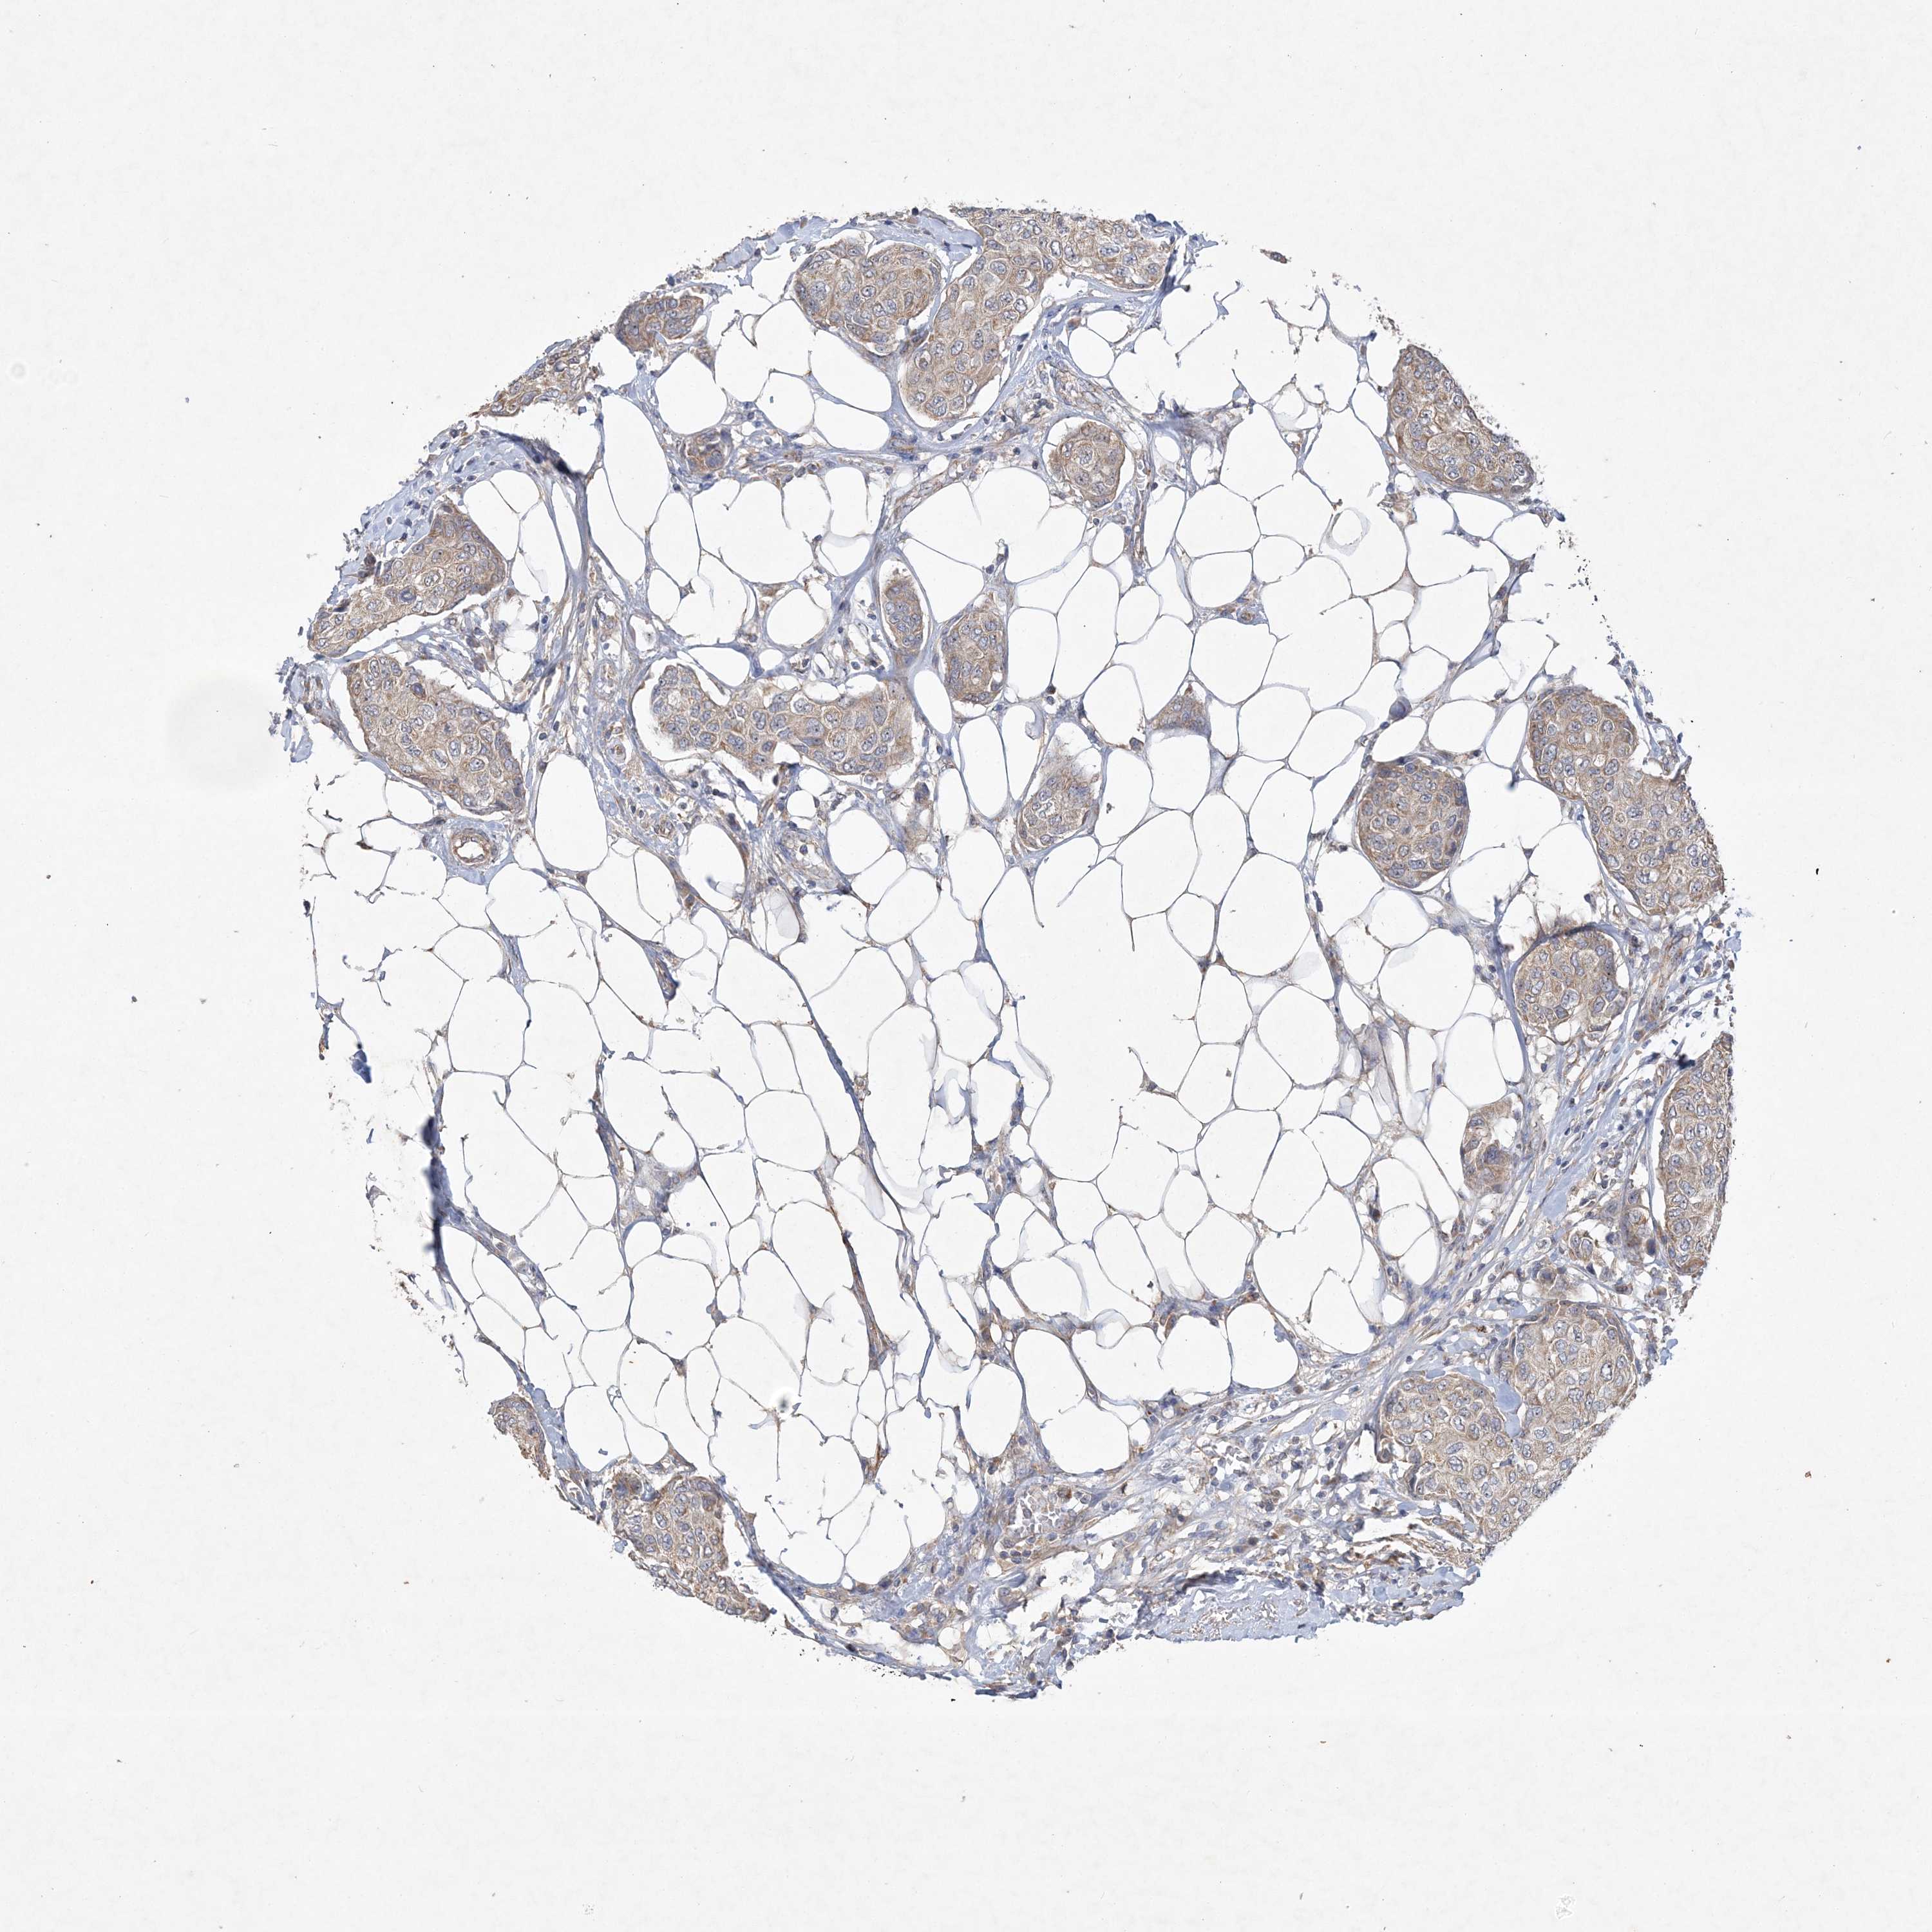

CANCER BREAST CANCER Show tissue menu

BRCA TCGA BRCA VALIDATION PROTEIN EXPRESSION